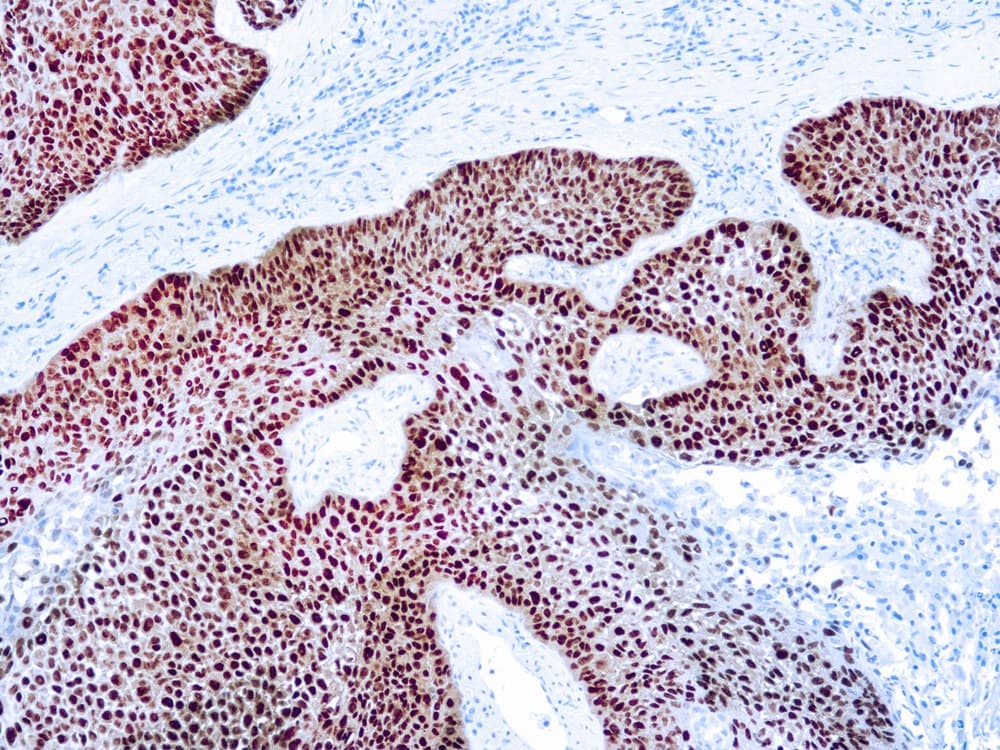

La p63 es una proteína supresora de tumores muy similar a la p53 en estructura y función, y homóloga a la p73. P63 se identifica en las células basales de las capas epiteliales de diversos tejidos, como la epidermis, el cuello uterino, el urotelio, la mama y la próstata. p63 es importante en el desarrollo y la diferenciación, y se ha identificado como un marcador útil para distinguir entre carcinomas de células escamosas de pulmón y adenocarcinomas. Se ha demostrado que p63 es un prometedor marcador específico de células basales complementario a la citoqueratina de alto peso molecular (HMW-CK), para el diagnóstico diferencial de lesiones prostáticas benignas y carcinoma prostático. El anti-p63 también se utiliza para diferenciar entre lesiones benignas y malignas de próstata y mama, debido a su marcaje de los núcleos de las células mioepiteliales en ambos tipos de tejido.

Sección de carcinoma de células escamosas de pulmón